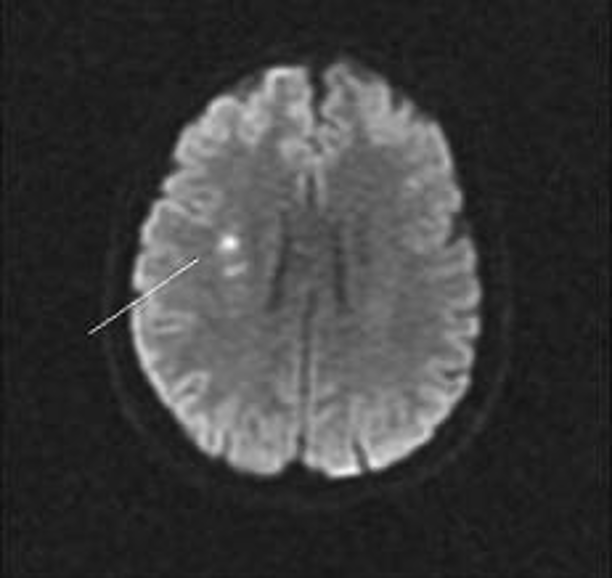

What type of scan can be used to identify damage caused as a result of TIA?

Diffusion-weighted MRI imaging shows areas of cytotoxic oedema